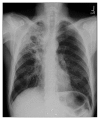

Bronchoesophageal Fistula due to Esophageal Tuberculosis

This is a case report regarding a patient who presented with 6 months of dysphagia and subsequent 40-pound weight loss. The patient underwent imaging, suggestive of pulmonary TB. Further workup of his dysphagia with esophagogastroduodenoscopy and bronchoscopy revealed two bronchoesophageal fistulas. Tuberculosis is an important differential diagnosis of prolonged dysphagia in immunocompetent patients.